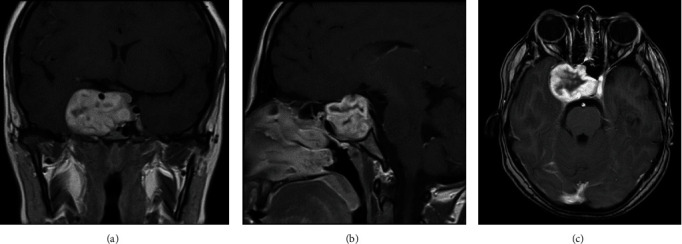

Background: Schwannomas are well-encapsulated, solitary tumors that grow slowly from the nerve sheath. Sellar schwannomas tend to be mistaken for other sellar/parasellar lesions due to similar clinical and radiological findings. The present article describes the clinical presentation, radiological findings, histopathological features, and outcome of a patient with sellar schwannoma. Case Description: A 23-year-old female, known to have hypothyroidism secondary to Hashimoto's thyroiditis, presented with multiple episodes of galactorrhea, weight gain, and irregular menstrual cycle for 8 months. It was associated with decreased visual acuity and episodic headaches. Neurological examination revealed no focal deficits. Brain magnetic resonance imaging (MRI) showed a well-defined lobulated lesion in the sellar region, compressing the right optic nerve and optic chiasm. The patient underwent craniotomy and tumor resection. The histopathological sections were diagnostic of schwannoma. Postoperatively, the patient noted a subjective improvement in her visual acuity. She was discharged in stable condition with regular follow-ups at neurosurgery, endocrine, and ophthalmology clinics. Conclusion: Schwannoma of the sellar region is rare and can be misdiagnosed as pituitary adenomas. Preoperative hormonal profile and meticulous neuroradiological assessment narrow down the differential diagnosis for patients with sellar lesions. The diagnosis of sellar schwannomas is established with histopathology and immunohistochemistry results.